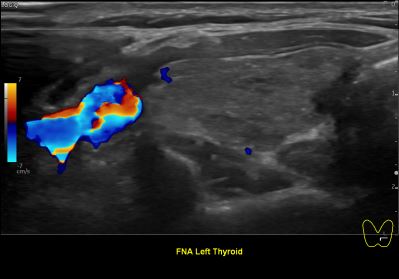

상기환자 외부건진 갑상선 이상소견으로 조직검사위해 내원하신 30대 중반 여성분으로

의심스러운 갑상선 좌엽 세포검사후 갑상선암으로 진단되었습니다